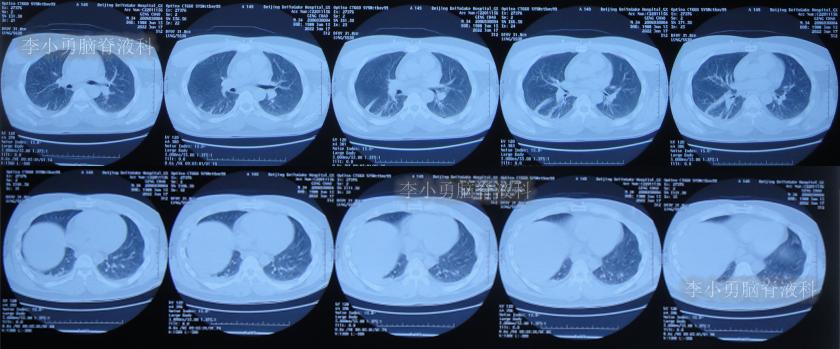

半月后即2022年6月17日,第3次住入李小勇脑脊液科,入院时:进食差,言语混乱,记忆力差,行走差(图-52);查头颅CT示右侧颞角增大,四脑室也稍大(图-53);肺部CT有感染(图-54)。

图-54:肺部CT